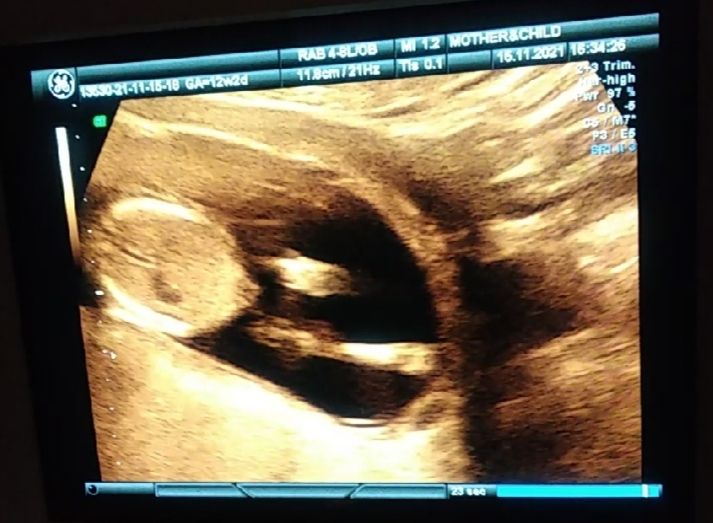

Клюква, спасибо, есть еще такое фото Изображение

Юлия , тут я не пойму. А сбоку видно половой бугорок. Торчит как у мальчика

Клюква, мне кажется это не бугорок, в странном месте для бугорка. Это наверное кусочек пуповины.

Елена, может и так) в любом случае мы больше угадываем.

Елена, просто под углом снимала)

Елена, если он будет ниже, то это уже точно будет девочка, мне кажется

VSV, я тут пуповину не вижу, только бугорок, Пуповина ж с середины животика

Юлия , это и есть середина живота. На бугорок не похоже совсем, хоть и торчит))) Он ниже.

VSV, думаю, все же Бугорок, врач то тоже по нему определил

Юлия , определил прям по этому скрину или, все-таки, во время УЗИ? Понятно, что по бугорку, просто на вашем скрине на бугорок не похоже. Желаю, чтобы в животике был сынок, как вы хотите!

VSV, спасибо) по узи, это скрин с видео, вот на видео кроме него не появляется никакого другого бугорка) наверное, вас сбивает, что под углом сделано